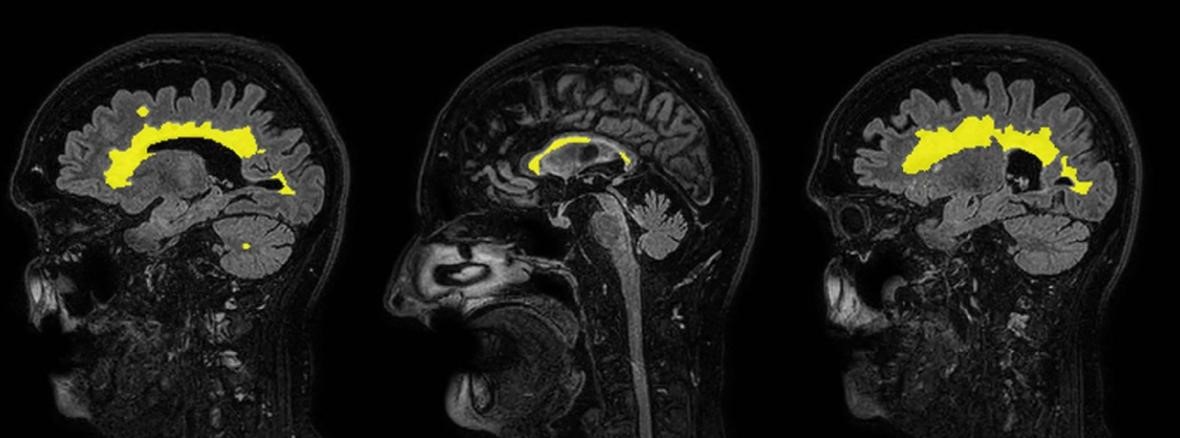

El segundo paciente femenino de 51 años tenía antecedente de esclerosis múltiple de más de 10 años de evolución en control evolutivo. Se analizaron las imágenes convencionales que mostraban estabilidad en la carga lesional sin evidencia de nuevas lesiones ni lesiones activas y signos de involución cerebral. En el reporte de Inteligencia artificial se mostró segmentación de lesiones en secuencia FLAIR, la cuantificación precisa del número de lesiones y su volumen total. También se cuantificó el grado de atrofia y se observó un volumen cerebral global por debajo del percentil 1 % para el grupo etario (Figuras 9 y 10).

Figura 9: Resonancia magnética de cerebro. Corte sagital flair.

Sagital FLAIR con segmentación de lesiones desmielinizantes

Figura 10: Reporte desmielinizante. Detección de lesiones y volumen cerebral global.

Se señala con flechas la detección de lesiones y la volumetría. El volumen global del volumen cerebral (FPC) se encuentra por debajo del percentil 1 % para el grupo etario.